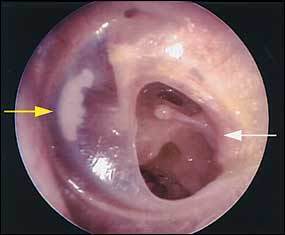

Describe image:

Image:

Answer

Causes: nasopharyngeal obstruction, otitis barotrauma, COM, epistaxis

Causes: nasopharyngeal obstruction, otitis barotrauma, AOM, allergic rhinitis

Symptoms: Deafness, tinnitus occasionally

Uncommon in small children